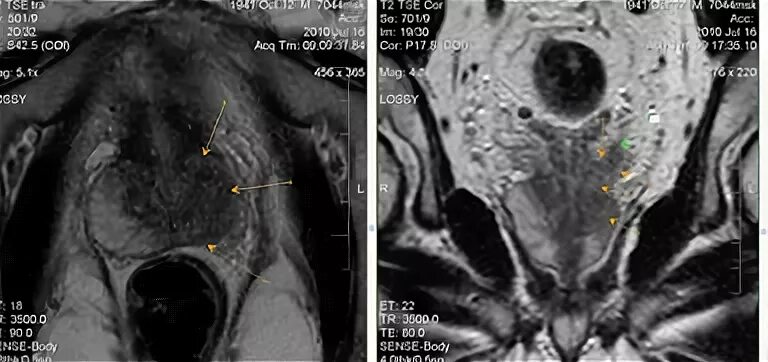

Простатит везикулит